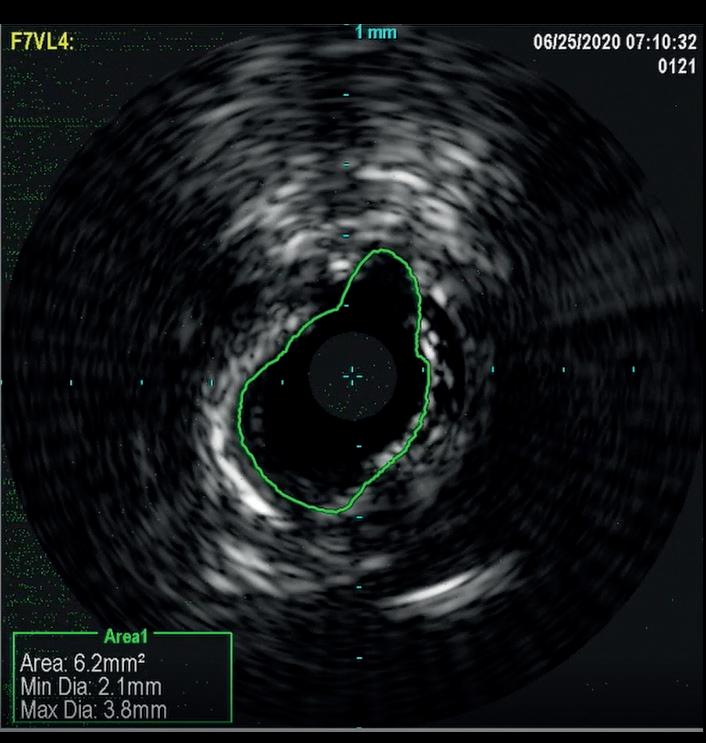

In a similar fashion, IVUS was used to evaluate elastic recoil following the use of IVL in a 61-year-old female patient with a history of diabetes, hypertension, high cholesterol, chronic kidney disease, and coronary artery disease. She presented with left lower extremity rest pain. Her baseline angiography showed two target areas with calcified stenotic disease that were treated (distal SFA and TPT). As shown in Figure 2, there was only an 8.8% loss of luminal gain in the max calcium portion of the TPT vessel 15 minutes after IVL treatment. Based on early and limited evaluations, IVL shows promising results with excellent luminal gain and with minimal luminal compromise, as evidenced on IVUS. Anecdotal cases have been encouraging and further studies are warranted to better understand if this mechanism of action provides the ability to ultimately produce significant luminal gain with minimal acute recoil. If this hypothesis holds true, this technology may lead to

Figure 2b. IVUS image 15 minutes after IVL treatment